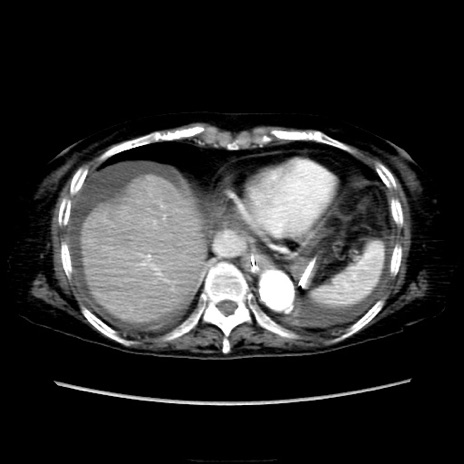

症例40(横断像)

【症例】90歳代女性

【主訴】腹痛・嘔吐

【現病歴】 食欲低下、嘔吐があり昨日他院受診。肺炎と診断され入院となる。入院後より腹部全体に圧痛あり。胃管留置され経過みていたが、症状持続するため、

当院転院となる。

【既往歴】胸椎圧迫骨折、胆石症

【身体所見】腹部:中央に激痛あり、圧痛あり、反跳痛不明

【データ】WBC 17100、CRP 18.82

横断像